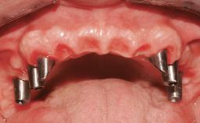

Fixed vs. Removable Prosthodontics for Restoring the Edentulous Maxilla

Fixed and removable prosthodontic implant therapy for restoration of the edentulous maxilla is both complex and challenging. Careful assessment and planning is needed in each individual case to explore whether a fixed or a removable solution will be the more suitable to satisfy the patient’s preference for optimal esthetics, phonetics, comfort and function. This Learning Pathway explores the prosthodontically driven treatment planning based on structured assessment, considered diagnosis and practical application in clinical case examples.

• recognize the importance of a prosthodontically driven plan and of planning implant configurations and placement accordingly